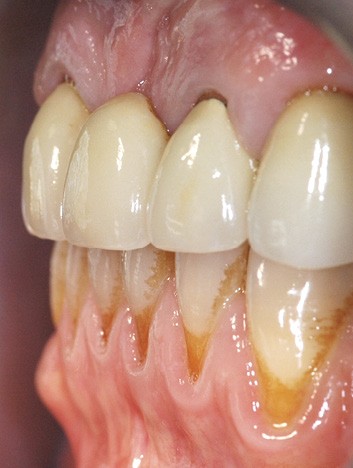

Il débute par l’évaluation des paramètres gingivaux (ligne du sourire [2], biotype parodontal [3], présence ou absence de papilles interdentaires, alignement des collets…). Les paramètres dentaires (origine de l’édentement, état de restauration des dents adjacentes, forme des couronnes dentaires…) compléteront cet examen (fig. 1). L’origine de l’édentement ne doit pas être sous-estimée. Graetz et al. [4] ont démontré que les patients avec des antécédents de maladie parodontale avaient une perte osseuse marginale et des profondeurs de poches plus importantes que les patients avec un parodonte sain.